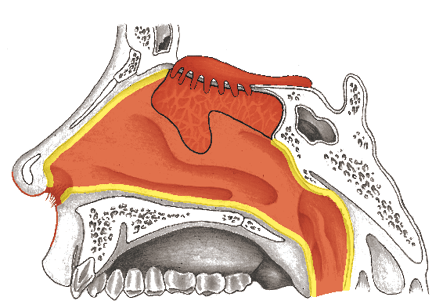

The nasal cavity (cavum nasi) is connected to the four hollow sinuses between the nose and eyes (sinus paranasales) by narrow canals. The sinuses of the cheeks (sinus maxillaris), the sinuses of the forehead (sinus frontalis), the sinuses behind the eyes (sinus sphenoidalis), the ethmoidal cells (cellulae ethmoidales), also between the nose and eyes, and the nasal cavity are lined with endodermal intestinal mucosa and the ectodermal squamous epithelium that lies over it.